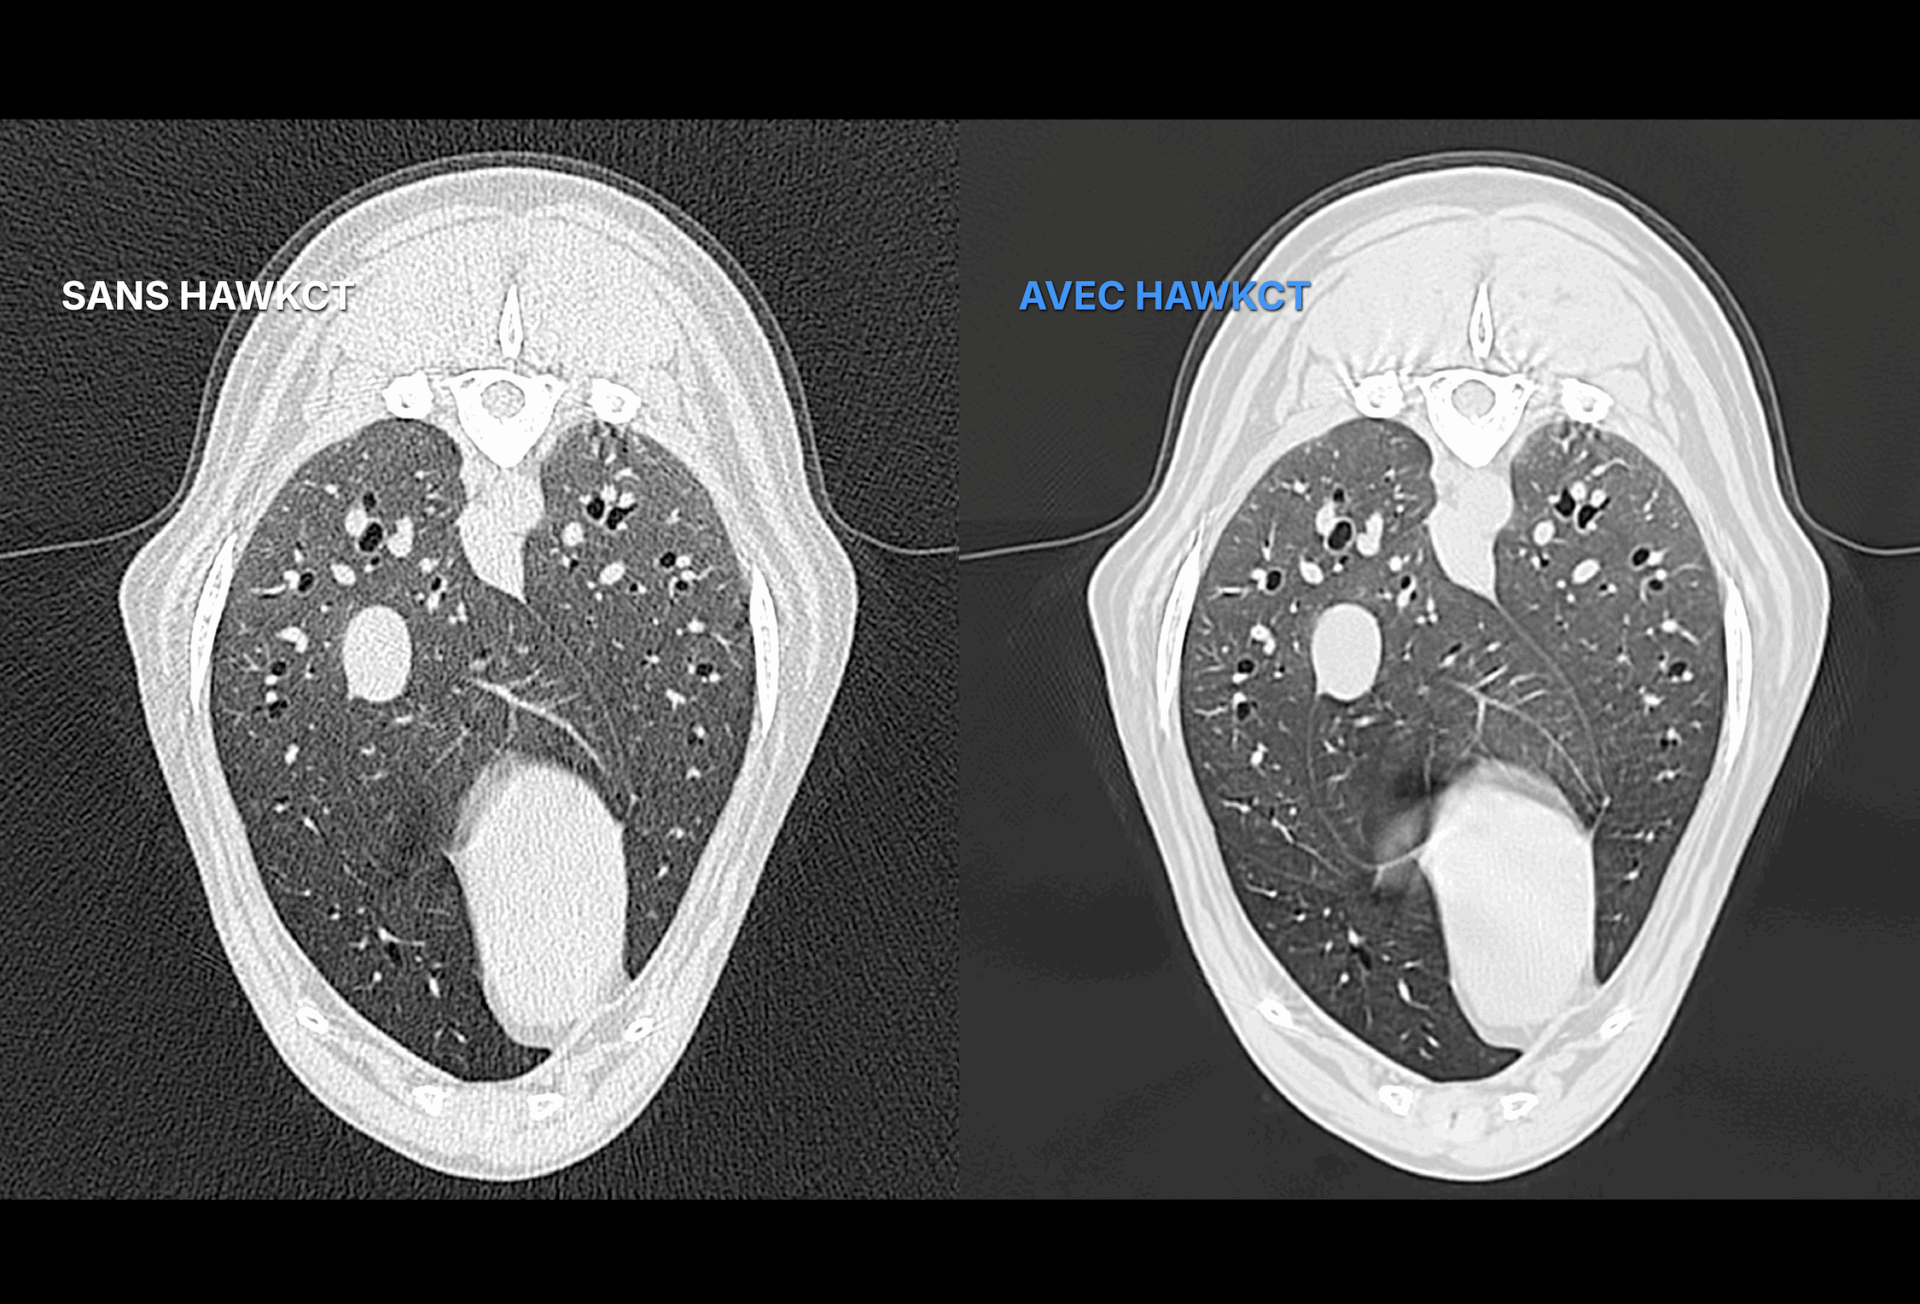

Sa reconstruction avancée renforce le contraste et la résolution, garantissant une qualité d’image constante sur toutes les séquences. Exclusivement conçu pour les vétérinaires, entraîné et validé sur des données animales, HawkCT permet aux cliniques d’accéder à une imagerie scanner plus rapide, plus sûre et plus durable.